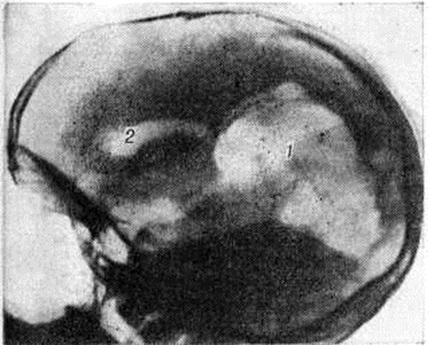

Рис. 3.

Пневмоэнцефалограмма при истинной порэнцефалии (боковая проекция): внутримозговая киста (1), имеющая широкое сообщение с боковым желудочком (2).

Порэнцефалия устанавливают на основании признаков органического поражения головного мозга и данных пневмоэнцефалографического исследования (смотри полный свод знаний: Пневмоэнцефалография). При истинной Порэнцефалия с помощью пневмоэнцефалографии выявляют кистозные полости, сообщающиеся с желудочками мозга, при этом желудочки обычно подтянуты к области дефекта ткани мозга (рисунок 3). Соустье между кистой и желудочком мозга определяется на пневмоэнцефалограмме, если диаметр его составляет не менее 2 миллиметров.: Расположенные в глубине мозга небольшие полости, сообщающиеся с желудочком мозга очень узким ходом, представлены на рентгенограммах как отшнурованные кистозные полости.